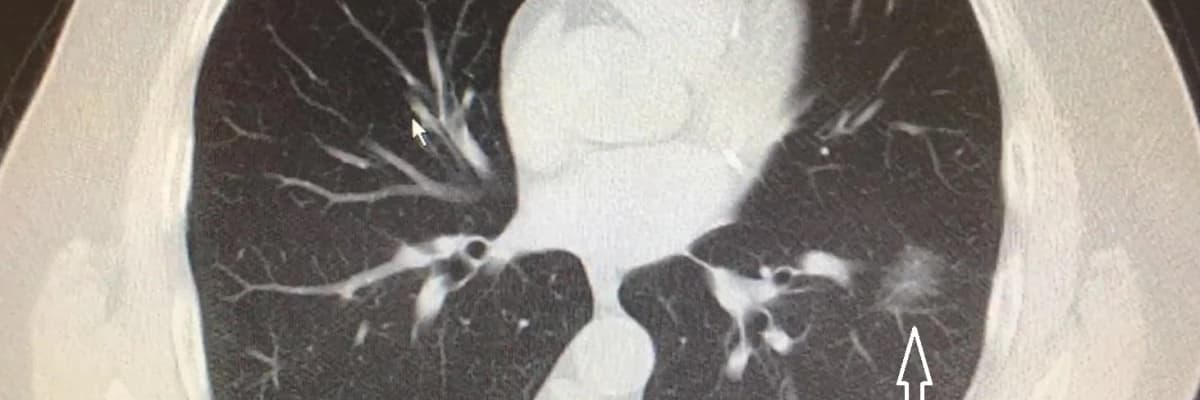

Nodülün kıvamına tomografi ile karar veriyoruz. Tomografi bize radyasyon ışınları ile insan vücudunu istediğimiz kalınlıkta ve yönde dilimleyebilmemizi sağlıyor. 1 mm’den 10 mm’ye kadar. Böylece nodülü üç boyutlu olarak analiz edebiliyor, boyutunu, hacmini ve şeklini ortaya koyabiliyoruz. Bazı nodüller zatürreyi andırıyor. Bazıları ise denizkestanesini, küçük bir lastik topu veya yer elmasını andırabiliyor. Bu şekillerin hepsi bize nodülün kanser olup olmadığı konusunda fikir veriyor. 3 cm’den küçük dokulara nodül diyoruz, ama 1 cm sınırı bizim için önemli. Niye mi? Çünkü akciğer kanserini 1 cm’den küçük yakaladığımızda hastalarımızın neredeyse tamamını (%90’ın üzerinde başarı şansı var) iyileştirebiliyoruz. Bu oran 2 cm’de %80’e, 3 cm’de %70’e düşüyor. Boyut arttıkça akciğer kanserinden kurtulma ihtimalimiz tedricen azalıyor. %10 önemlidir, hele terazinin bir tarafında insan hayatı olunca daha da önemli hale geliyor.

Sigara içiyorsanız ve 55 yaşın üzerinde iseniz, akciğerinizde sert kıvamlı, kenarları düzensiz, 15 mmden büyük nodül görüldüyse, bunun kanser olma şansı %50. Sigara miktarı ve yaş arttıkça bu ihtimal daha da artıyor. Oysa sigara içmeyen ve 40 yaş altındaki kişilerde böyle bir nodülün kanser olma ihtimali %10’dan daha az… Yani sigara ve yaş karar verirken dikkate aldığımız en önemli iki kriter. Diğer önemli kriterler ailede akciğer kanseri hikâyesi, amfizem varlığı, cinsiyet, nodülün sertlik derecesi ve nodülün büyüklüğü. Hatta nodüllerin kanser riskini hesaplayan internet ve cep telefonu programları var. Makalenin başında yazdığımıza geri dönelim. Tesadüfen çekilen bir göğüs tomografisinde, 45 yaşında sigara içen bir erkekte 6 mm’lik bir nodül tespit edilirse ne yapacağız?